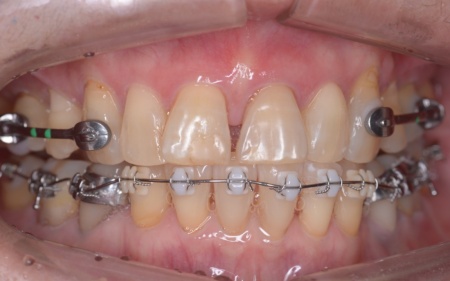

そのため、ワイヤー矯正である程度歯の移動を行ったのち、アライナー矯正(マウスピース矯正)で仕上げを行う矯正治療を提案し、同意いただきました。

・ワイヤー矯正

歯の表面にブラケットと呼ばれるボタン状の装置を接着し、そこにワイヤーを通して歯を移動させる矯正治療です。

まずはワイヤー矯正を行い、ある程度まで歯並びを整えます。